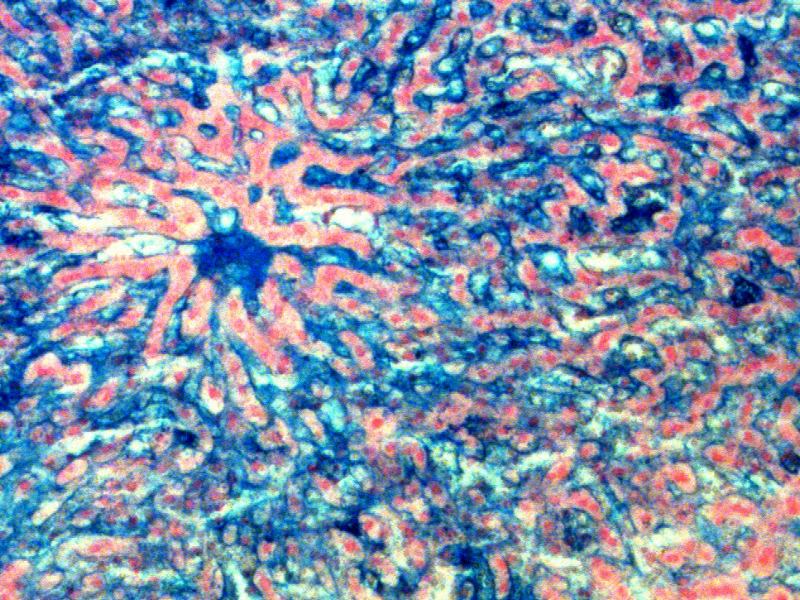

Portal vein vs Central vein

The portal vein is part of the portal triad. It has an associated artery and bile duct. The central vein has no other structures around it, and the endothelium is indistinct. You can most the times also see the sinusoids opening up into the central vein.

What is located with the vena centralis?

What is with the vena centralis?

Arteries?

Veins?

Bile ducts?

Lymph vessels?

Arteries - no

Veins - no

Bile ducts - no

Lymph vessels - no

Where do we find these structures?

Portal triad contains these structures.

So what about the portal artery, vein and bile duct?

Let's add these to our diagram...

ps: there is a lymph vessel as well

Compare the central vein and portal triad...